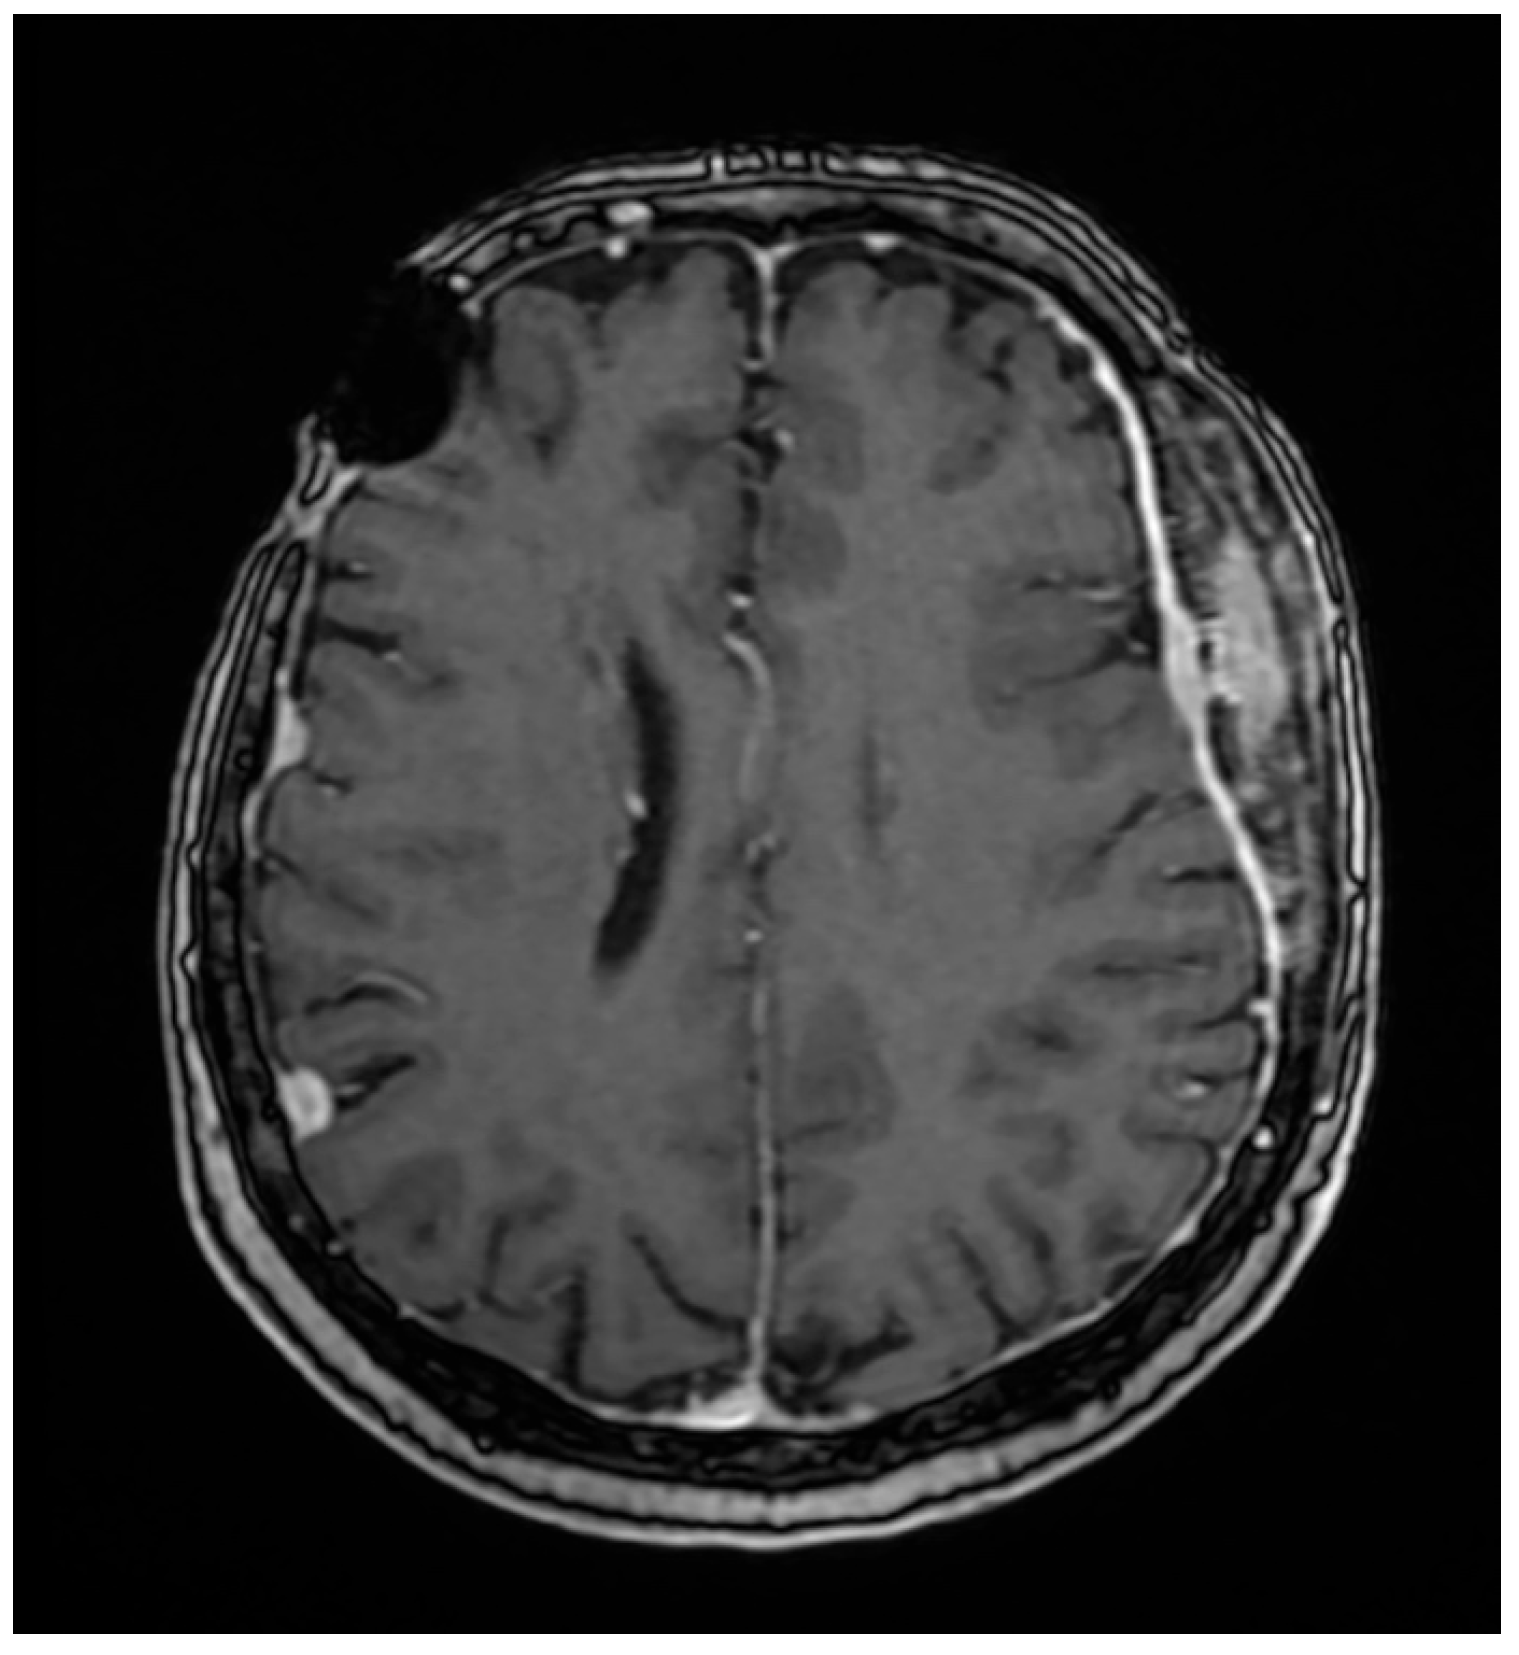

Her 2023 MRI revealed a porencephalic cavity following neurosurgical intervention, which communicated with adjacent cerebral sulci, resulting in secondary widening and perilesional gliotic changes. No contrast enhancement was observed. At the left fronto-temporo-parietal bone, tumor-related changes were noted, characterized by contrast enhancement, bone structural inhomogeneity, and extension both intracranially (extraneuraxial involvement) and into the soft tissues of the scalp. The central osteolytic area measured 49 × 22 × 76 mm (AP × LL × CC) and was surrounded by inhomogeneous osteosclerosis of the adjacent skull. The meninges appeared diffusely thickened with mild irregularities and contrast enhancement. Additionally, discrete edema was observed in the temporal muscle and adjacent fat tissue. The MRI also demonstrated stable findings of multiple right-sided meningiomas (frontal, temporal, and parietal), a left temporal meningioma, and a fronto-temporo-parietal intraosseous meningioma (Figure 1). The magnetic resonance examination was performed on a 1.5 Tesla MRI machine (SignaTM Explorer General Electric, GE Healthcare, Fairfield, Waukesha, WI, USA; MR software release: SV25.2_2127a).

Given her history of multiple meningiomas, a neurosurgery consultation was obtained. MRI revealed no progression of the previously identified meningiomas (Figure 4), and the skin lesion was found to be adjacent to the intraosseous meningioma. Skin ultrasound of the lesion demonstrated soft tissue infiltration consistent with meningiomatosis. Additional investigations, including mammography and a gynecological exam, showed no abnormalities.

Figure 1. MRI examination with iv contrast media, axial 3D T1 FSPGR (14 February 2023). MRI (2023) showing a porencephalic cavity in the left fronto-temporo-parietal region, post-neurosurgical intervention. Tumor-related changes include a large central osteolytic lesion (49 × 22 × 76 mm) with irregular bone structure and soft tissue extension. Surrounding inhomogeneous osteosclerosis, diffuse meningeal thickening, and mild temporal muscle edema are noted. No contrast enhancement is seen in the porencephalic cavity. Stable multiple meningiomas are also present.

Figure 4. The same examination 16 months later revealed the same aspect, without significant changes.